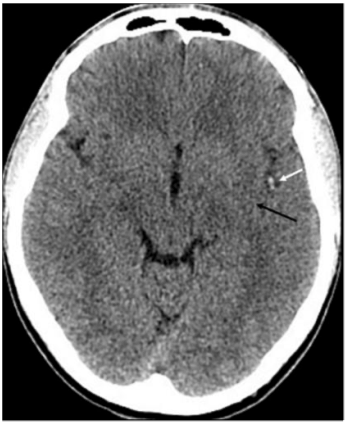

22세 남자가 호흡곤란으로 입원하였다. 환자는 3년 전 항인지질항체증후군(antiphospholipid syndrome)을 진단 받았다. 한 달 전 고속버스를 타고 장시간 여행한 후부터 오른쪽 장딴지에 통증이 있었으며, 10일 전부터 시작된 호흡곤란이 내원 하루 전부터 급격히 악화되었다. 흉부 컴퓨터단층촬영(Computed tomography, CT)에서 양측 폐동맥 색전증(사진 A의 A, B, C, 흰색 화살표)과 심장의 심방중격결손(atrial septal defect)이 발견되었다(사진 A의 D, 검은색 화살표). 입원 4일째 갑자기 발생한 오른쪽 상지와 하지의 근력 약화로 시행한 뇌 CT 에서 왼쪽 중대뇌동맥 주변에서 뇌경색 소견이 관찰되었다(사진 B의 흰색 화살표). 이 환자에게서 뇌경색이 발생한 이유를 가장 잘 설명한 용어는?

(사진 A)